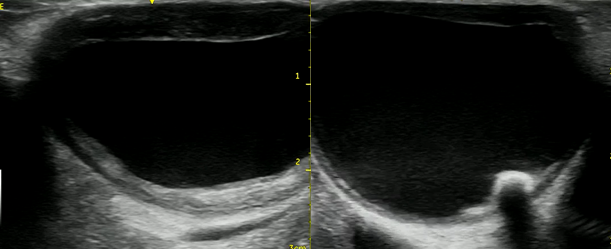

Каротидную эндартерэктомию всем пациентам выполняли под общей анестезией. Практически во всех случаях использовалась классическая методика с пластикой артериотомии ксеноперикардиальной заплатой. Перед пережатием сонных артерий вводился гепарин в расчете 1,5 мг/кг, после запуска кровотока проводилась нейтрализация гепарина протамина сульфатом. В обязательном порядке использовался интраоперационный мониторинг с помощью церебральной оксиметрии в ближнем инфракрасном диапазоне (рис. 2). Среднее время пережатия сонных артерий в обеих группах составило 23,7 ± 6,6 и 24,6 ± 6,5 мин соответственно. Ни в одном случае не был использован внутрипросветный шунт. У части пациентов также была осуществлена отдельным этапом реваскуляризация сонных артерий с противоположной стороны.

Рис. 2. Показатели церебральной оксиметрии при КЭЭ. Отмечено время наложения и снятия зажимов с сонных артерий